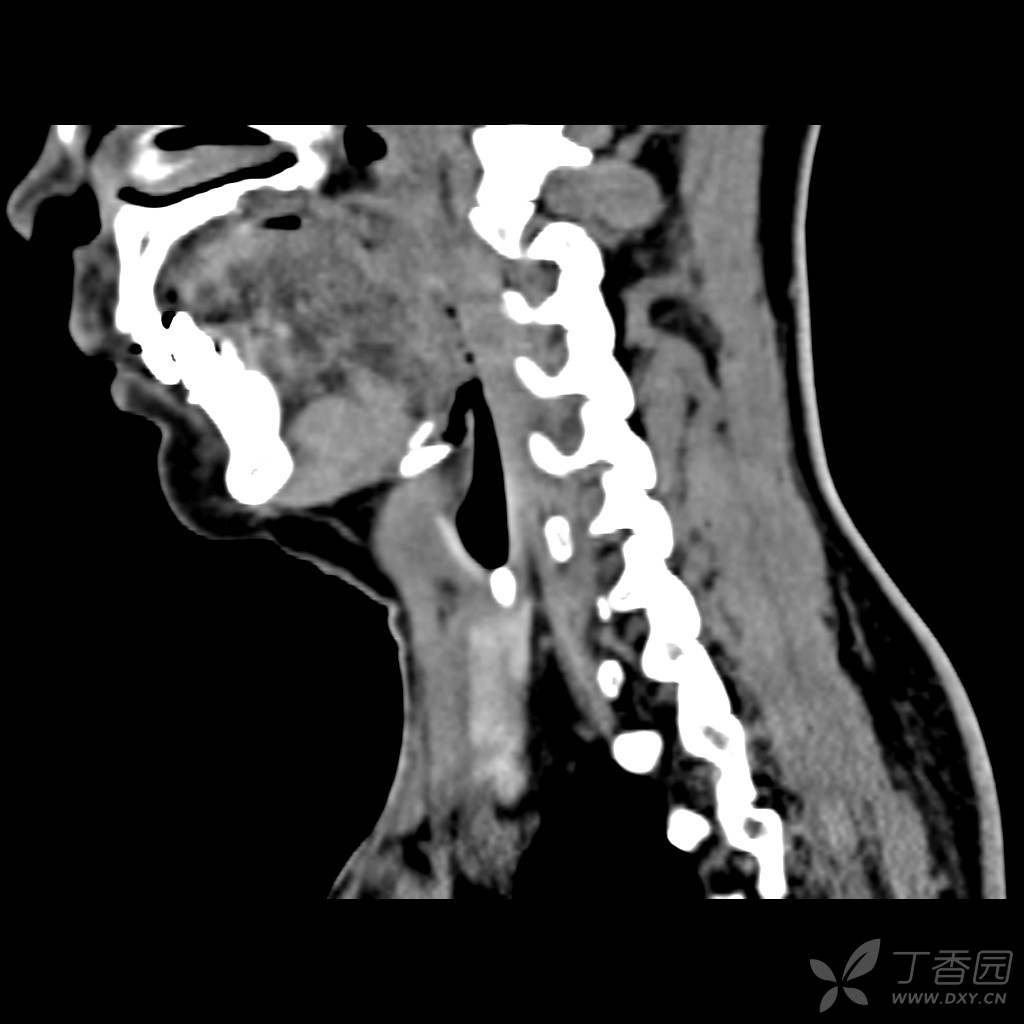

1例成人甲状舌管囊肿的ct表现

图片尺寸1390x1962